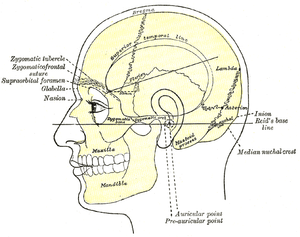

Base of skull. Muscle attachments are shown in red lines. Side view of head, showing surface relations of bones. (Mastoid process labeled near center.)

Side view of head, showing surface relations of bones. (Mastoid process labeled near center.)